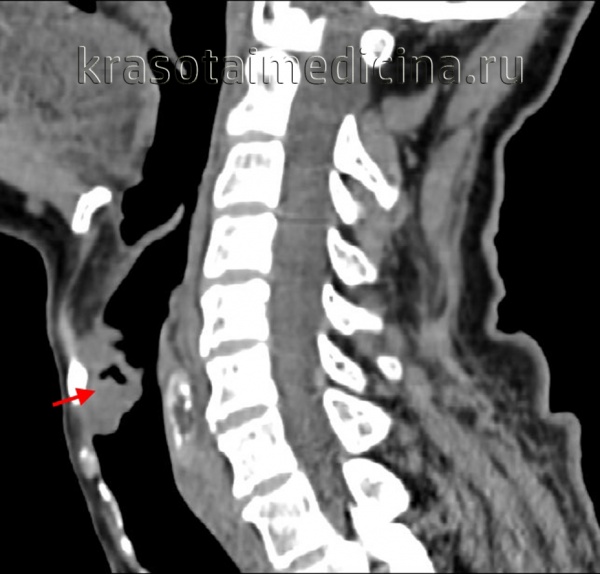

- Компьютерная томография (КТ) дает возможность определить размеры опухоли и ее распространение по лимфатическим узлам и окружающим тканям;

При постановке диагноза учитывают результаты КТ и МРТ гортаноглотки и УЗИ шеи. Решающую роль в выявлении рака гортаноглотки играют данные фиброфаринголарингоскопии. При проведении исследования специалист осуществляет визуальную оценку размера, локализации и структуры новообразования, а затем выполняет биопсию подозрительного участка. Окончательный диагноз выставляют онкологи на основании гистологического исследования.